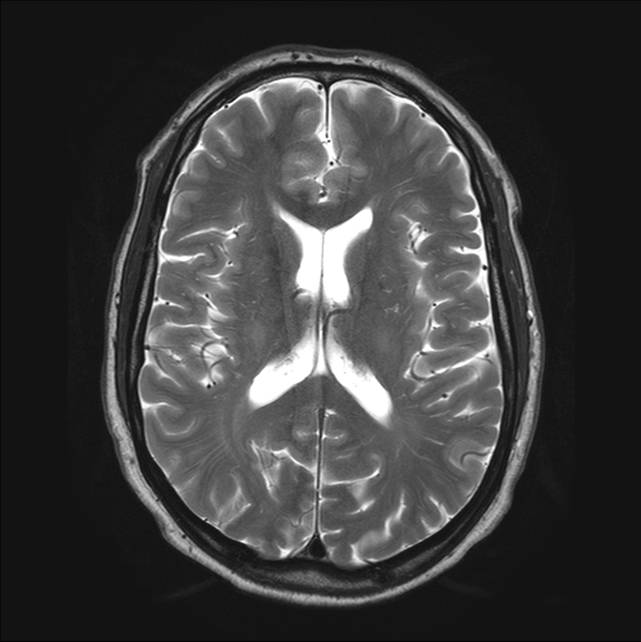

Billede 1: Normal hjerne, tværsnit (set oppefra).

MR-billederne viser fire forskellige optagelser af en normal hjerne. Cerebrospinalvæsken er hvid på billede 1 og 3, mens den er sort på 2 og 4. Man ser tydeligt forskellen på grå og hvid substans i hjernen, det ses bedst på 2 og 4.